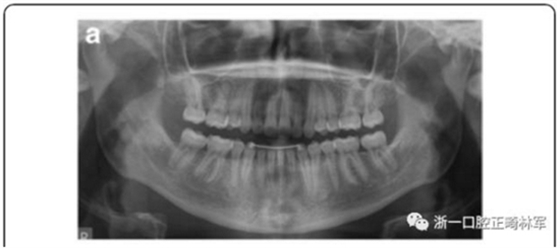

影像學檢查,右側(cè)第二前磨牙和所有第三磨牙先天性缺失;

10周后,根據(jù)臨床和影像,形成乳磨牙牙槽粘連,移除牙弓夾板。下一步,在右下第一磨牙上粘接帶環(huán),在第二乳磨牙和下頜第一前磨牙上粘接托槽,在恒磨牙和乳磨牙之間安裝T型曲前移第一恒磨牙。T型曲共激活9次。

第6個月,臨床和影像檢查顯示乳牙幾近完全的替代性牙根吸收和間隙的完全關(guān)閉。最終,將乳磨牙拔除并開始進行完整的正畸治療。在接下來一年,用0.017’’*0.025’’末端回彎的不銹鋼弓絲和彈性牽引剩余間隙關(guān)閉,并以II類牽引作為支持。

治療結(jié)果

雙側(cè)I類尖牙和磨牙關(guān)系;完全的間隙關(guān)閉(用牙線確定);覆合覆蓋糾正;仍有輕度的中線偏離。頭測分析顯示,下切牙未發(fā)生舌側(cè)移動。